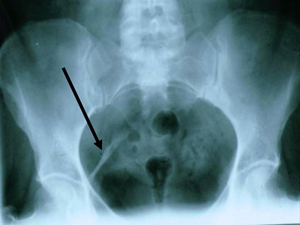

DISH generally affects at least 2 or more levels of the spine, and most often, 97% of cases, affects the thoracic spine.